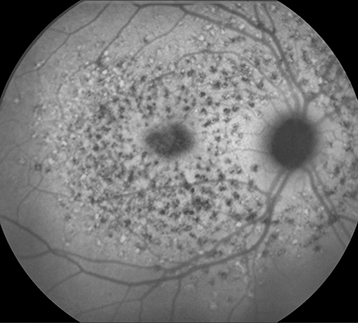

(See Figures 11.30.1 to 11.30.3.)

Yellow or yellow-white, fleck-like deposits at the level of the RPE, often in a pisciform (fish-tail) configuration.

Atrophic macular degeneration: May have a bulls eye appearance as a result of atrophy of the RPE around a normal central core of RPE, a beaten-metal appearance, pigment clumping, or marked GA.

Vermilion or light-brown fundus with obscuration of choroidal vasculature. Atrophy of the RPE just outside of the macula or in the midperipheral fundus, normal peripheral visual fields in most cases, and rarely an accompanying cone or rod dystrophy. Peripapillary sparing best seen by FAF. The ERG is typically normal in the early stages but may become abnormal late in the disease. The EOG can be subnormal.

IVFA often shows blockage of choroidal fluorescence producing a silent choroid or midnight fundus as a result of increased lipofuscin in RPE cells.

FAF can be helpful in diagnosis and in monitoring disease progression.